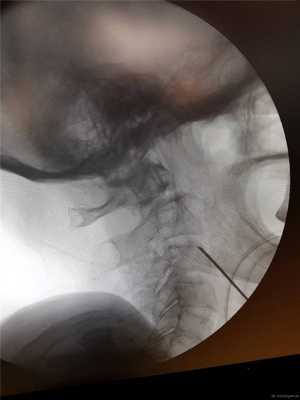

Затем под рентгеновским контролем устанавливается спица в необходимой точке ввода под нужную траекторию.

Контроль в прямой проекции.

Спица проводится дрелью до верхушки С2. Затем так же проводится и вторая.